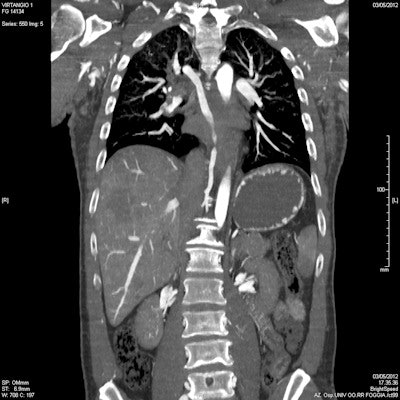

Due to its strengths in visualizing bone structure and detecting embolisms and gross abnormalities in soft tissue, CT has been widely used in forensic pathology for some time. Its advantages over MR in terms of the availability of equipment, relative simplicity, and the time constraints inherent in examining corpses, have made it the dominant modality in forensic imaging. The recent development of volumetric measurement has given this lead a further boost by introducing the ability to obtain images in different ways and focus more specifically on areas of interest.

"Spiral volumetric computed tomography is largely responsible for the incredible recent development of the role of diagnostic imaging in forensic medicine. If you are looking for specific details in the skin, you can make a reconstruction of the skin; if your investigation centers on the skeleton, you can reconstruct bones; and if you are looking at organs, you can reconstruct the soft tissue. You can manipulate the images to find the exact answer you are looking for," said session chairman Dr. Giuseppe Guglielmi, from the University of Foggia in Italy.

Thanks to the development of specially created contrast techniques, CT can also be used to investigate the postmortem vascular system. Multiphase postmortem CT angiography (MPMCTA), which involves the performance of one native CT scan and three angiographic phases (arterial, venous, and dynamic), allows the vascular system to be imaged in a similar way to standard clinical CT angiography. A mixture of paraffin oil and a specially created oily contrast agent is injected via a device that reproduces the conditions of perfusion in a living body, enabling the radiologist to capture highly accurate images of any abnormalities in the vascular bed of the viscera, or lesions of the vascular system.